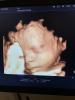

Отзывы о 3D УЗИ в клиниках Эскулап и Архангельска

Кто-нибудь ходил в Эскулап бьют и в Архангельске на 3д узи?

стикер